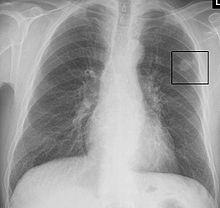

老年人肺癌为原发于支气管-肺的癌,即原发性支气管肺癌,简称肺癌。肺癌是世界上对人类健康与生命危害最大的恶性肿瘤。该病是随着原发灶的发展过程及肿瘤所在部位、肿瘤大小、对支气管的影响、邻近气管是否受侵犯或压迫、远隔脏器是否有转移、是否有异位内分泌特性等因素的不同,而出现各种不同的临床表现。